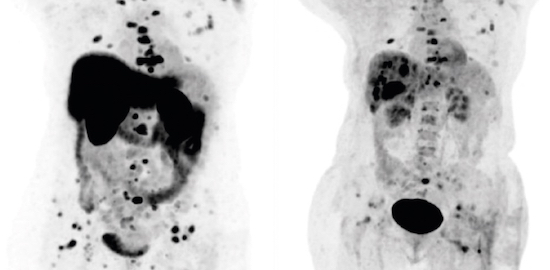

Översikt Vid stark misstanke om glomustumör ska patienten remitteras till en av Sveriges två nationella högspecialiserade enheter